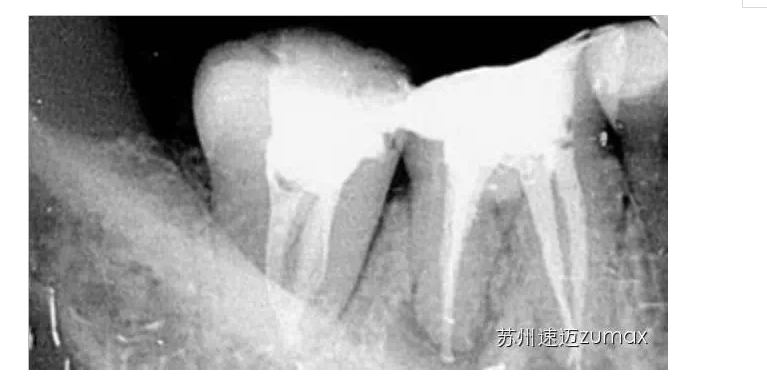

二、C形根管的識別

成功治療C形根管的前提是要正確識別,即判斷C形根管是否存在以及大致形態(tài)。僅從臨床牙冠的形態(tài)很難判斷C形根管是否存在,可通過X線技術(shù)、顯微鏡或內(nèi)窺鏡檢查以及CBCT檢查識別C形根管。

C形根管的治療最好是在手術(shù)顯微鏡下進行。上橡皮障后開髓,去除髓室中的牙髓組織,使用DG16仔細探查根管口位置,然后用10或15號不銹鋼K銼探查根管的形態(tài)、直徑和走向。當(dāng)根管口呈連續(xù)的C形時,插入根管內(nèi)的診斷銼為2~4個,通常為3個。當(dāng)根管口呈分號形時,可以在較小的根管內(nèi)插入1個診斷銼,在較大的根管內(nèi)插入1~3個診斷銼。